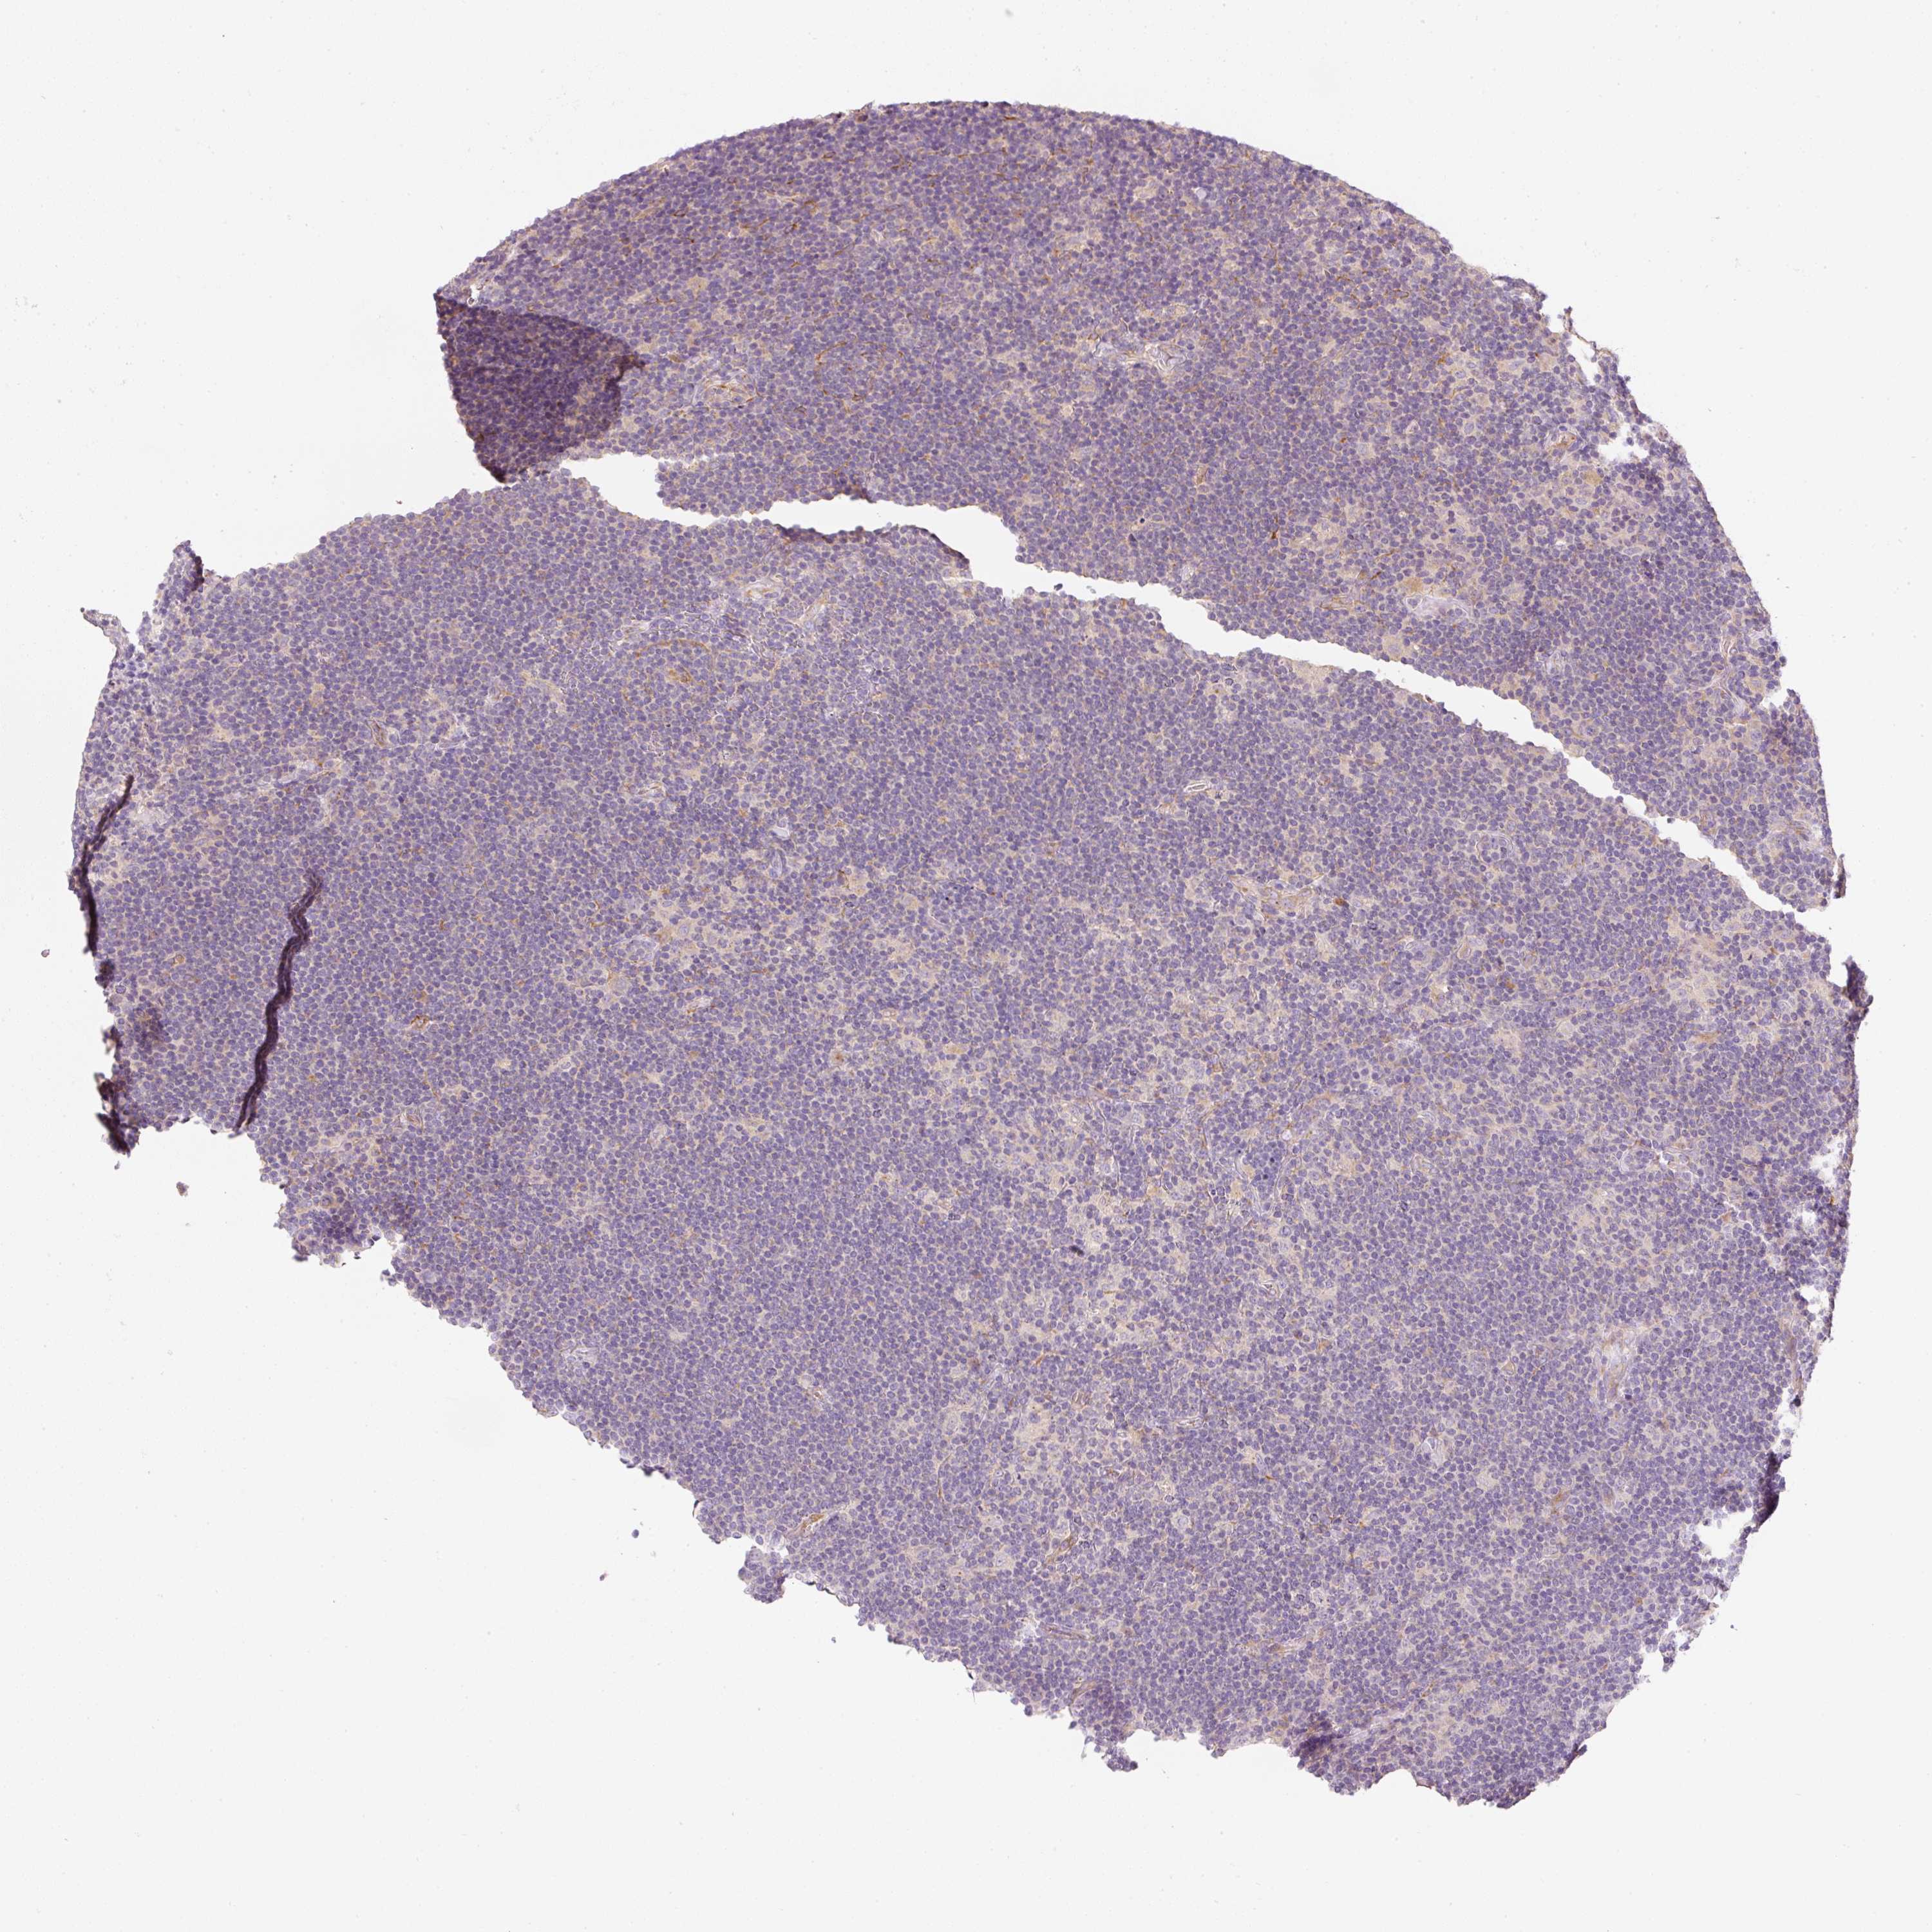

LYMPHOMA - Protein expressioni

A mouse-over function shows sample information and annotation data. Click on an image to view it in a full screen mode. Samples can be filtered based on level of antibody staining by selecting one or several of the following categories: high, medium, low and not detected. The assay and annotation is described here.

Antibody staining in the annotated cell types in the current human tissue is reported as not detected, low, medium, or high, based on conventional immunohistochemistry profiling in selected tissues. This score is based on the combination of the staining intensity and fraction of stained cells.

Each image is clickable and will lead to virtual microscopy that enables deeper exploration of all samples and also displays staining intensity scores, fraction scores and subcellular localization as well as patient and tissue information for each sample.

Antibody HPA049810

Staining

High

Medium

Low

Not detected

Intensity

Strong

Moderate

Weak

Negative

Quantity

>75%

75%-25%

<25%

None

Location

Nuclear

Cytoplasmic/membranous

Cytoplasmic/membranous,nuclear

Hodgkin's disease, NOS

Malignant lymphoma, non-Hodgkin's type, High grade

Malignant lymphoma, non-Hodgkin's type, Low grade